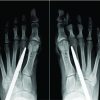

A 50-year-old female patient presented to our pain clinic in November 2017 with chief complaints of pain (burning), swelling, cold peripheries, and blackening of all five fingers of the right (Fig. 1c and d) and four fingers of the left (except thumb) hands (Fig. 1a and b) for the past 3 months. Pain was present during rest, increasing while lifting hands and relieving on bringing down. Diagnosis was made based on clinical examination and the color Doppler study of both upper limbs (Table 1). The patient was consulted with a colleague surgeon who referred the patient.

Under all aseptic precautions, 4-5 stellate ganglion blocks were given [accurate needle position (Fig. 2a) was confirmed in anteroposterior and lateral fluoroscopic view (Fig. 2a and c) and craniocaudal dye spread of dye (Fig. 2b) and excluding intravascular position] simply with 0.25% bupivacaine with 4 mg of dexamethasone (only once on both sides) on an alternate day basis using a 22G spinal needle under all aseptic precautions and C-Arm (fluoroscope) guidance at C6 level. After such blocks, chemical neurolysis was successfully done with 2 ml of 8% phenol mixed with 2 ml of 0.25% bupivacaine and 1 ml of radiocontrast non-ionic iodine dye, iohexol 300 under continuous fluoroscopic guidance (to avoid intravascular spread and apical pleura puncture) at C7. Phenol was injected after confirmation of needle position at the junction of the vertebral body and transverse process (Fig. 2a) at C7 in anteroposterior and lateral (Fig. 2c) view and with craniocaudal spread (Fig. 2b) of dye (1 ml, iohexol 300) with the excluding intravascular injection of dye (Fig. 1g, and 2b and c) 10 days apart on both sides (Fig. 1i and Fig. 2b and c) to avoid cardiac complications (bradycardia) and bilateral recurrent laryngeal nerve palsy. After the successful accomplishment of the procedure, there was an increase in the temperature of the hands, an improvement in vascularity and a reduction in swelling and pain. There was a dropping of eyelids, enophthalmos and conjunctival congestion for a transient period. The patient was monitored after every block for at least 2 h in the post-procedure room. In due course of time, the affected salvageable portion of the fingers was saved (Fig. 1e, f and h). The patient was kept on a tramadol-paracetamol combination, pregabalin 75 mg at bedtime, asprin 75 mg once daily, cilastazole 100 mg twice a day, and isosorbide mononitrate 10 mg twice a day by oral route. The patient was followed up for 5-6 months when the gangrenous part was detached from the healthy part (Fig. 1j). Recently till February 2024, there was no recurrence of disease as evident from telephonic contact.